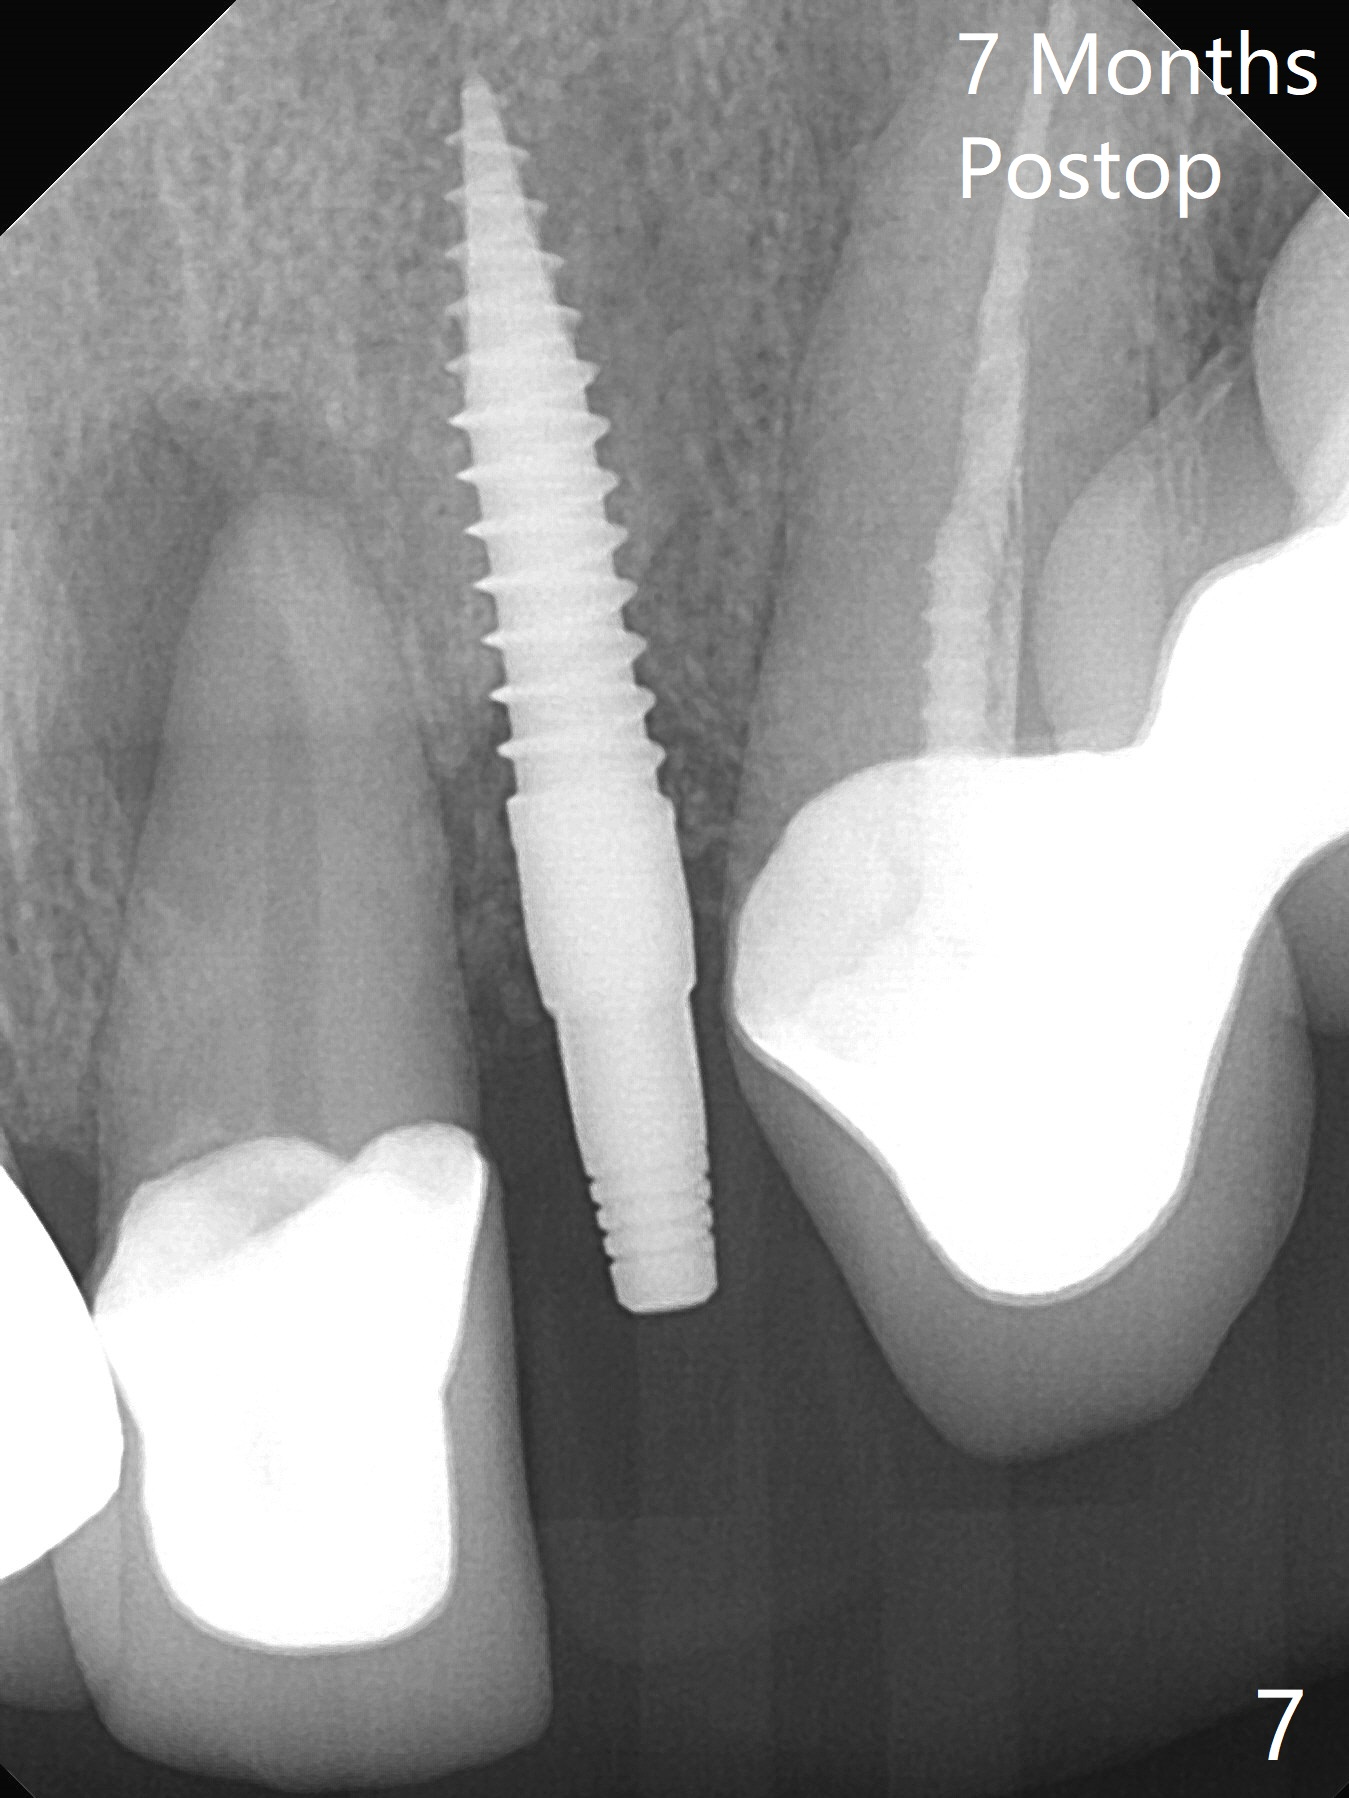

The tooth #10 fractures at the cervix, but is attached to the gingiva.  After extraction of the coronal portion of the tooth, the mesiodistal space palatally is found to be narrow (~4.7 mm, Fig.1).  It appears that a 1-piece implant is indicated because of the narrow mesiodistal space.  In fact the buccal plate of the socket is intact (Fig.2).  The initial osteotomy seems to be mesial (Fig.1) and is moved distal using Lindamann bur.  After sequential osteotomy, a 3x10 mm dummy implant is still mesial (Fig.4).  Following further distalization, a 3x14 mm implant is placed (Fig.5,6; <30 Ncm).  Vera Graft is placed in the remaining socket prior to provisional fabrication (Fig.6 *).  The socket outline disappears 7 months postop (Fig.7).  Panoramic X-ray is taken 1 year 3 month post cementation.